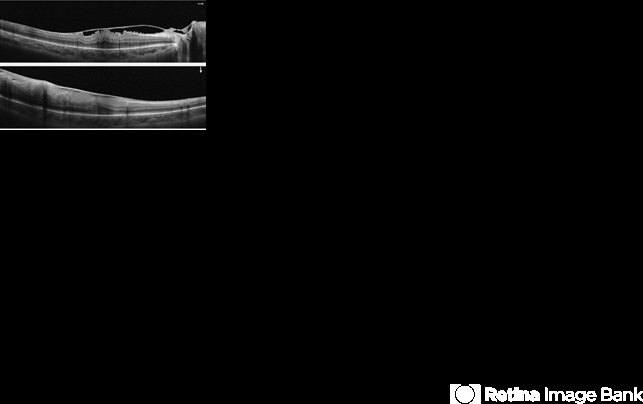

- Coats' disease, optical coherence tomography (OCT)

- Macular OCT in a coats disease with epiretinal membrane.